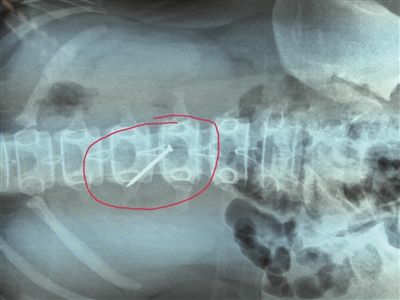

长约4厘米的铁钉被取出时,已刺穿13岁女生的胃壁。 朱鼎兆 摄

一根长近4厘米的铁钉在胃里会怎么样?29日下午4时许,在淮安市妇幼保健院,该院小儿科医生就从宿迁泗阳一名13岁女生小轩(化名)的胃里成功取出一根长约4厘米的铁钉,而此时,这根铁钉已经刺破了小轩的胃壁。